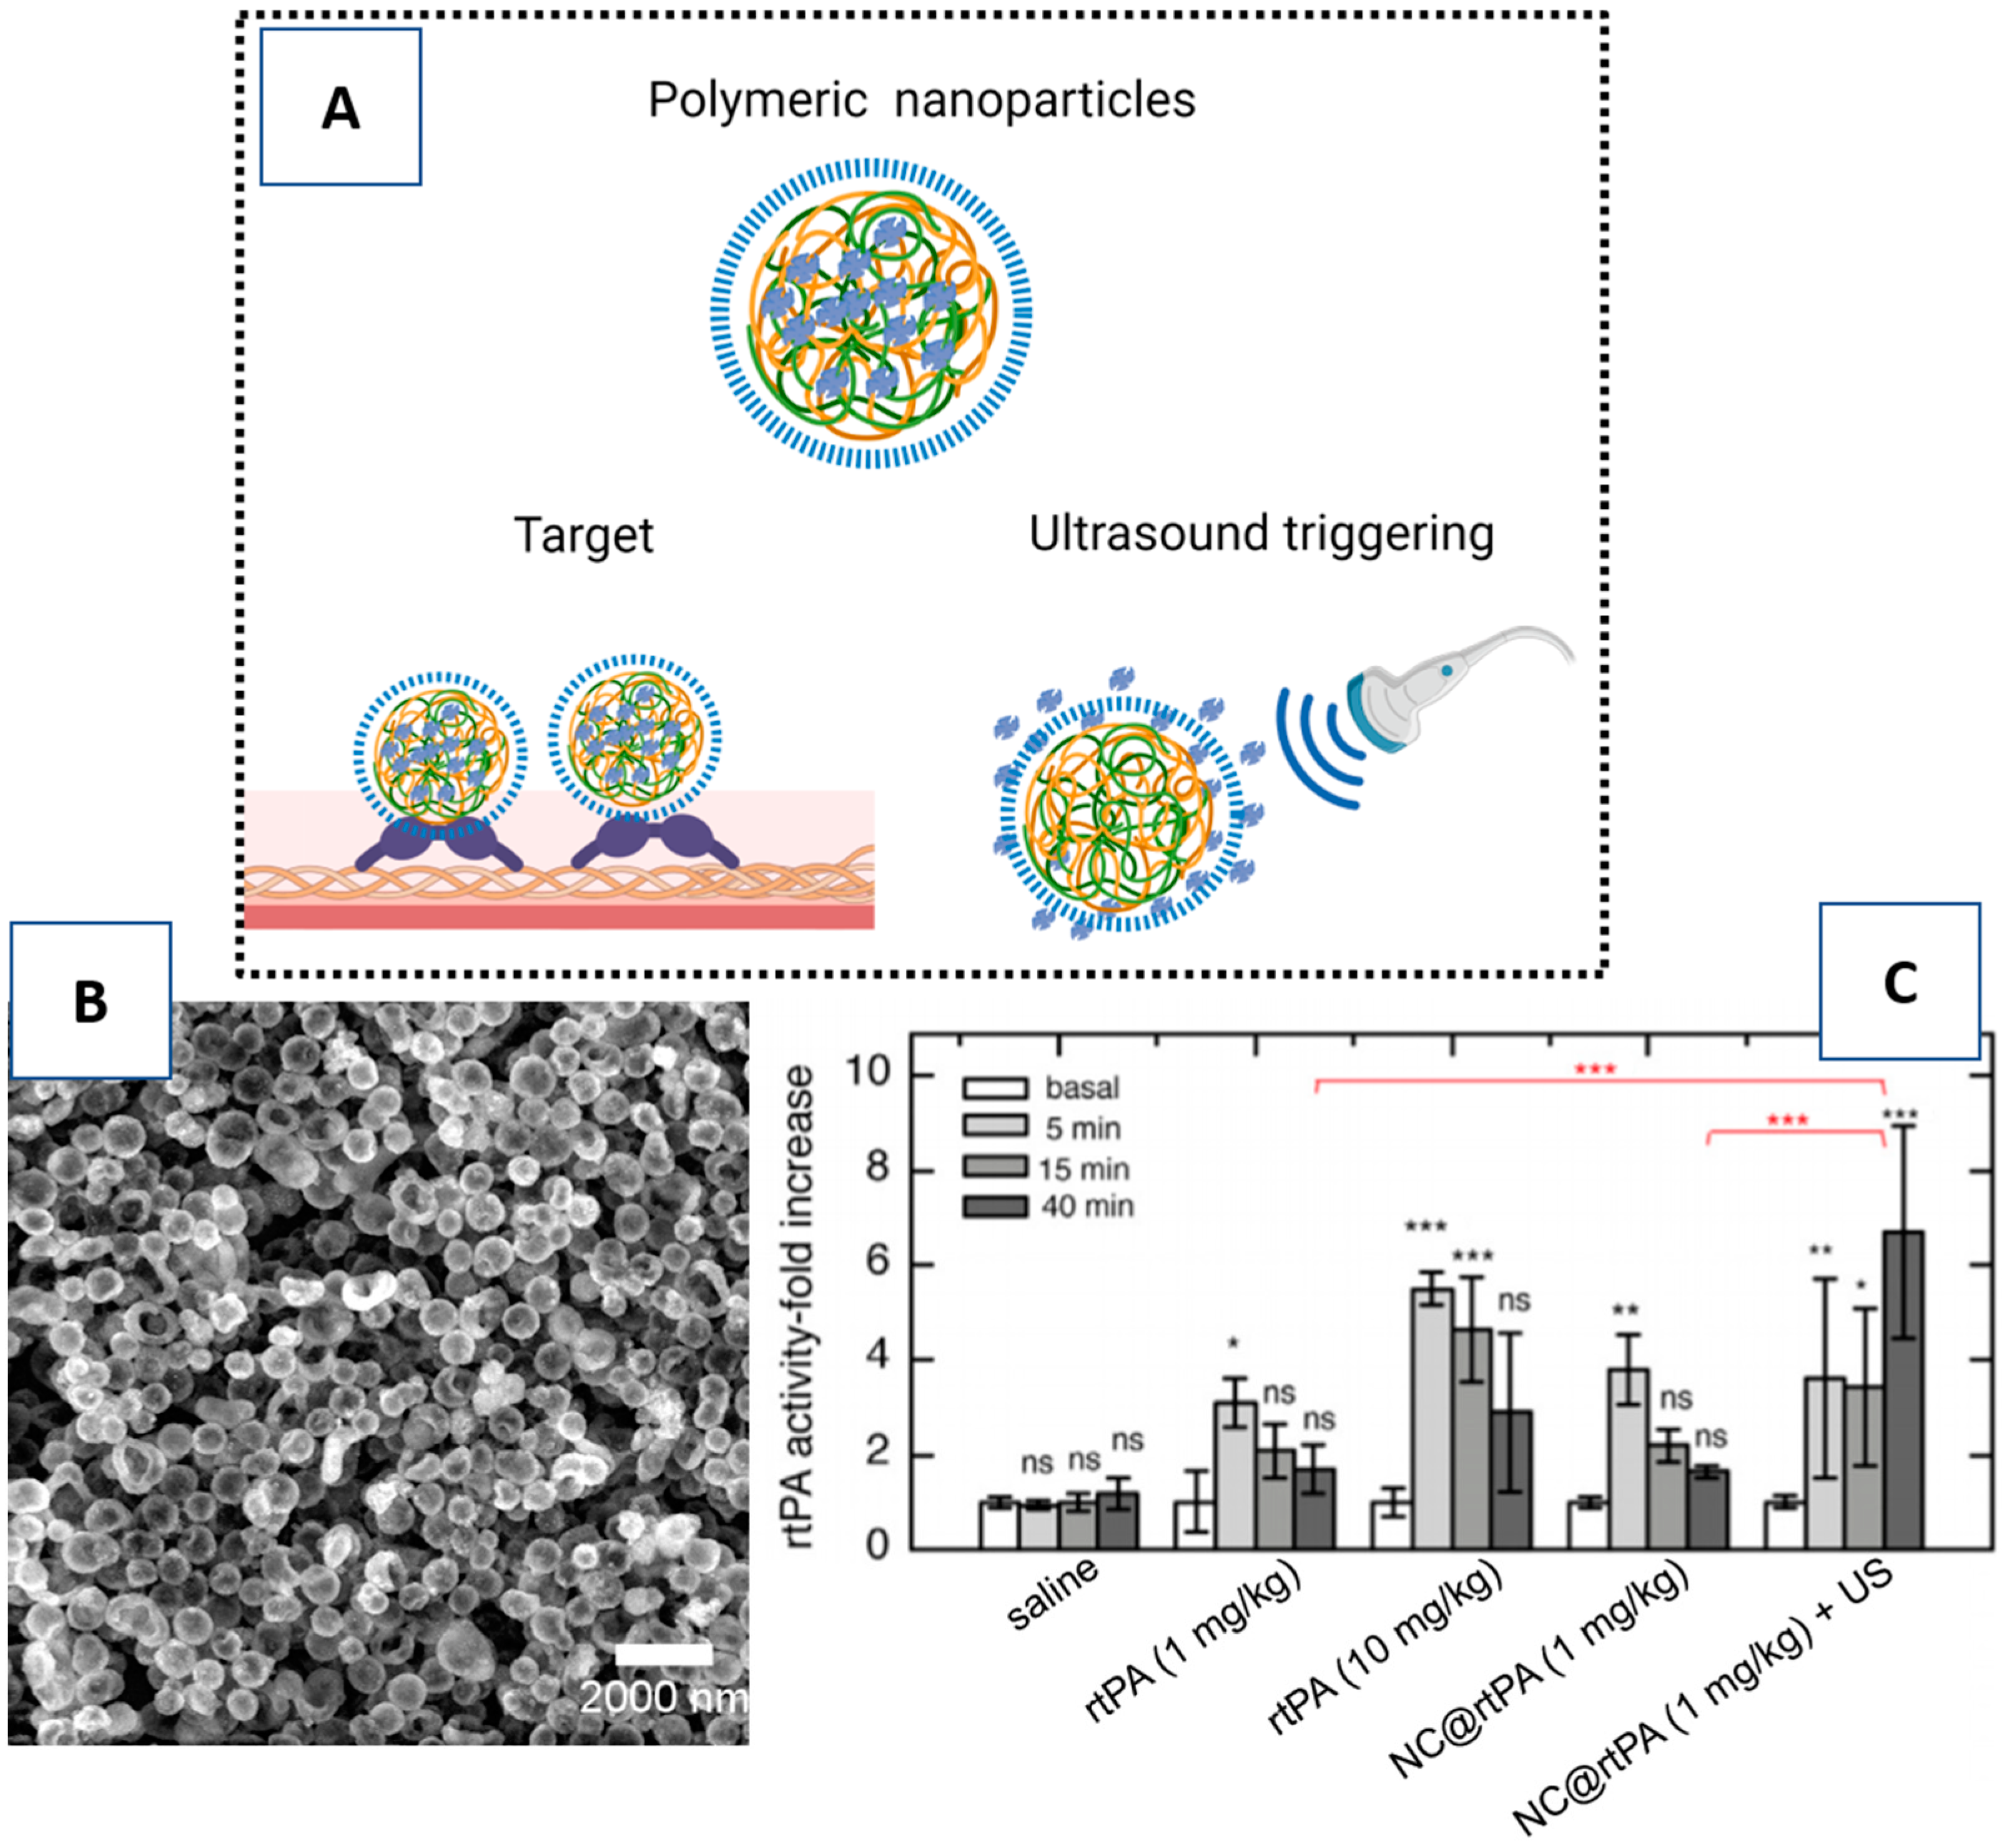

3.1. Nanocarriers for rtPA

3.3. Triggering Controlled Release

4. Nanoparticles as a Therapy for Ischemic Brain Protection

- Correa-Paz, C.; Poupard, M.F.N.; Polo, E.; Pérez, M.R.; Taboada, P.; Iglesias-Rey, R.; Hervella, P.; Sobrino, T.; Vivien, D.; Castillo, J.; et al. In vivo ultrasound-activated delivery of recombinant tissue plasminogen activator from the cavity of sub-micrometric capsules. J. Control. Release 2019, 308, 162–171. [Google Scholar] [CrossRef]